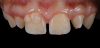

A 16-year-old female patient presented with the chief complaint that she was dissatisfied with the appearance of her anomalous maxillary lateral incisors (teeth Nos. 7 and 10) and multiple diastemas (Figure 1 through Figure 4). She had been referred for restorative treatment after an initial consultation with the orthodontist. Her first restorative appointment was dedicated to data collection, which included a health history and physical examination as well as the acquisition of photographs (facial, dentofacial, dental), videos (chief complaint, F sound, S sound), vinyl polysiloxane (VPS) impressions, a panoramic radiograph, a bite registration, and a facebow registration. The clinical examination revealed that both of the patient's maxillary lateral incisors were peg-shaped. After a discussion about the risks and benefits of different treatment options, such as direct composite restoration, indirect composite veneers, and porcelain laminate veneers, she chose to have her maxillary lateral incisors treated with direct composite buildup restorations. The index cutback technique was chosen for this case instead of a freehand technique in order to create a new shape according to an ideal wax-up but also to be able to control the thickness of the enamel layer.7

(1.) Pretreatment smile, left lateral smile, and right lateral smile photographs, respectively, showing the patient’s peg-shaped lateral incisors.

Figure 1